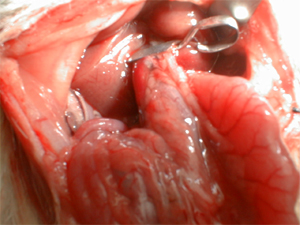

Isquemia hepática

| 1 | Puesta a punto de un modelo experimental para el estudio de la isquemia hepática normotérmica |

| 7 | Puesta a punto de un modelo experimental de isquemia hepática normotérmica intermitente |